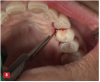

Fig 10. The removal of granulation tissue with a Younger-Goode 7/8 curette being used in a spoon motion is illustrated. The arrow points to the tip of the curette placed into the bony defect. The granulation tissue is removed in a fashion similar to the use of a caries spoon to remove caries.

Figure 10